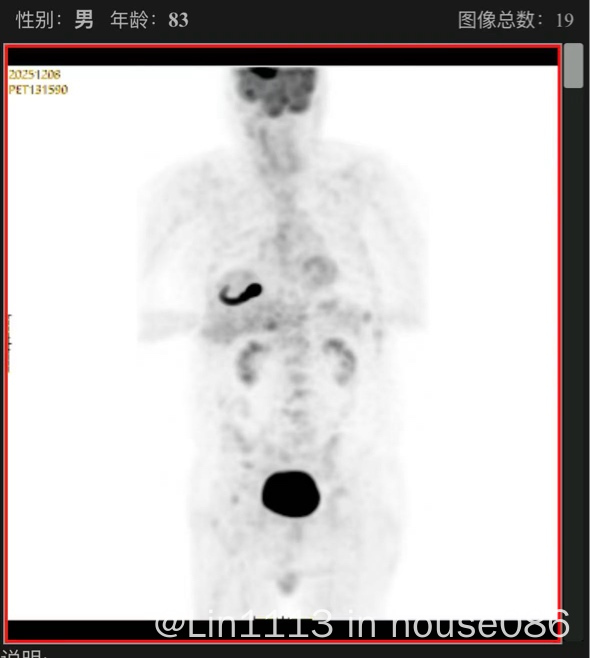

83岁,发现时颅内5.0x3.5x3.4cm。年龄大不开颅,经细胞因子,ctDNA,确诊淋巴瘤,又做petct看原发继发。

已经吃了两天泽布+来拿那